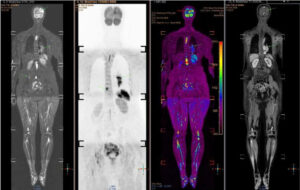

Giáo sư Khoa lo ngại về tỷ lệ thanh thiếu niên sử dụng thuốc lá và thuốc lá mới (như thuốc lá điện tử) vẫn ở mức cao, làm gia tăng nguy cơ ung thư phổi trong tương lai. Ông khuyến nghị tầm soát sớm cho những người có nguy cơ cao, như người hút thuốc chủ động hoặc thụ động. Chụp CT liều thấp có thể phát hiện tổn thương nhỏ, trong khi các kỹ thuật hiện đại như PET/CT, PET/MRI, kết hợp sinh học phân tử, giúp xác định đột biến gene và lựa chọn điều trị trúng đích hiệu quả.